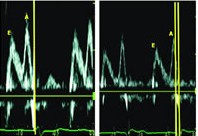

图1 AV间期优化前后的二尖瓣血流频谱图

CRT术后,将180 ms的AV间期程控至120 ms后,可见心脏舒张期充盈时间延长,心房充盈期延长。

4. 舒张充盈时间:二尖瓣舒张早晚期血流速度峰值(E峰与A峰)频谱完整、分离、峰值最大、左心室充盈时间最长、二尖瓣反流程度最小时所对应的AV间期最佳。